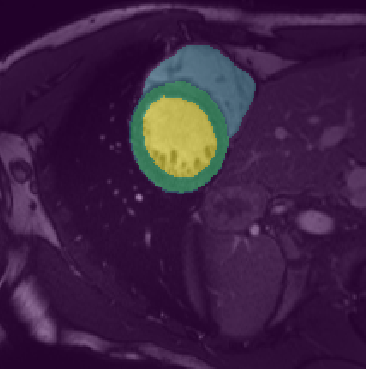

In this paper, we aim to improve the performance of semantic image segmentation in a semi-supervised setting in which training is effectuated with a reduced set of annotated images and additional non-annotated images. We present a method based on an ensemble of deep segmentation models. Each model is trained on a subset of the annotated data, and uses the non-annotated images to exchange information with the other models, similar to co-training. Even if each model learns on the same non-annotated images, diversity is preserved with the use of adversarial samples. Our results show that this ability to simultaneously train models, which exchange knowledge while preserving diversity, leads to state-of-the-art results on two challenging medical image datasets.